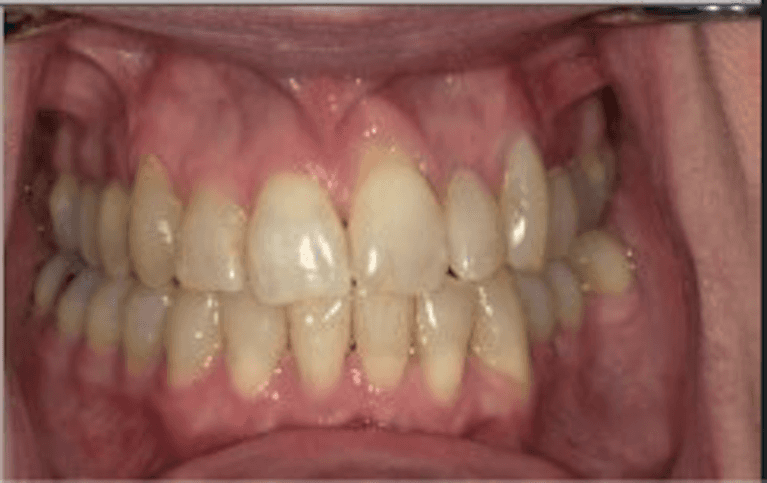

This patient came to Carewell Dental looking to address significant crowding and overlapping that had long affected her confidence. By utilizing a customized clear aligner treatment plan, we were able to gently guide her teeth into their ideal positions without the need for traditional metal braces. The result is a beautifully balanced, wider smile that not only improves her dental health but also perfectly complements her natural features. It’s a testament to how modern technology can deliver life-changing results right here in Rutland.